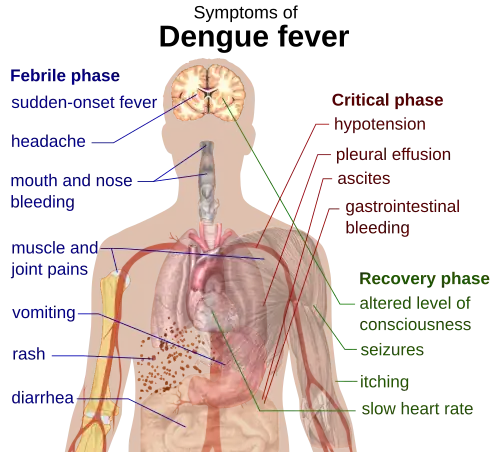

The course of infection is divided into three phases: febrile, critical, and recovery.[22]

The febrile phase involves high fever (40 °C/104 °F), and is associated with generalized pain and a headache; this usually lasts two to seven days.[1][23] There may also be nausea, vomiting, a rash, and pains in the muscle and joints.[1]

Most people recover within a week or so. In about 5% of cases, symptoms worsen and can become life-threatening. This is called severe dengue (formerly called dengue hemorrhagic fever or dengue shock syndrome).[22][24] Severe dengue can lead to shock, internal bleeding, organ failure and even death.[25] Warning signs include severe stomach pain, vomiting, difficulty breathing, and blood in the nose, gums, vomit or stools.[25]

During this period, there is leakage of plasma from the blood vessels, together with a reduction in platelets.[25] This may result in fluid accumulation in the chest and abdominal cavity as well as depletion of fluid from the circulation and decreased blood supply to vital organs.[24]

The recovery phase usually lasts two to three days.[24] The improvement is often striking, and can be accompanied with severe itching and a slow heart rate.[24]